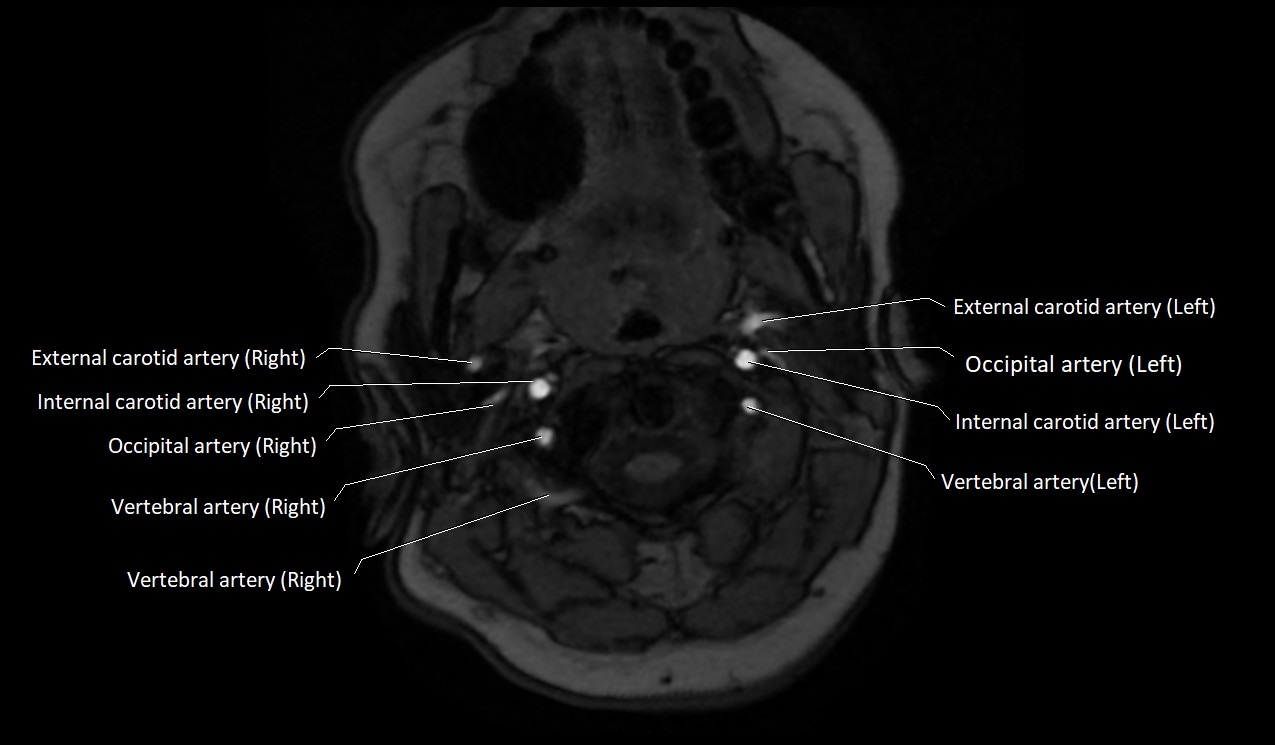

MRI images

image